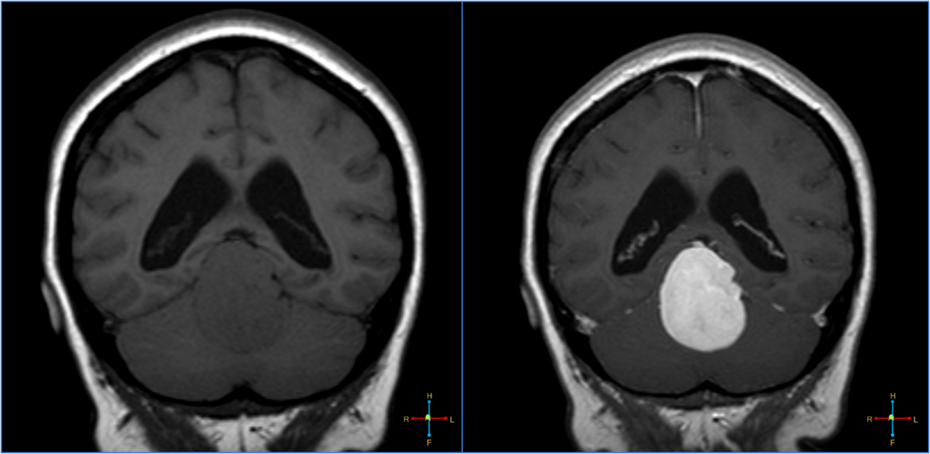

Brain MRI scans reveal that anxiety is independently associated with a faster progression from mild cognitive impairment to Alzheimer’s disease.